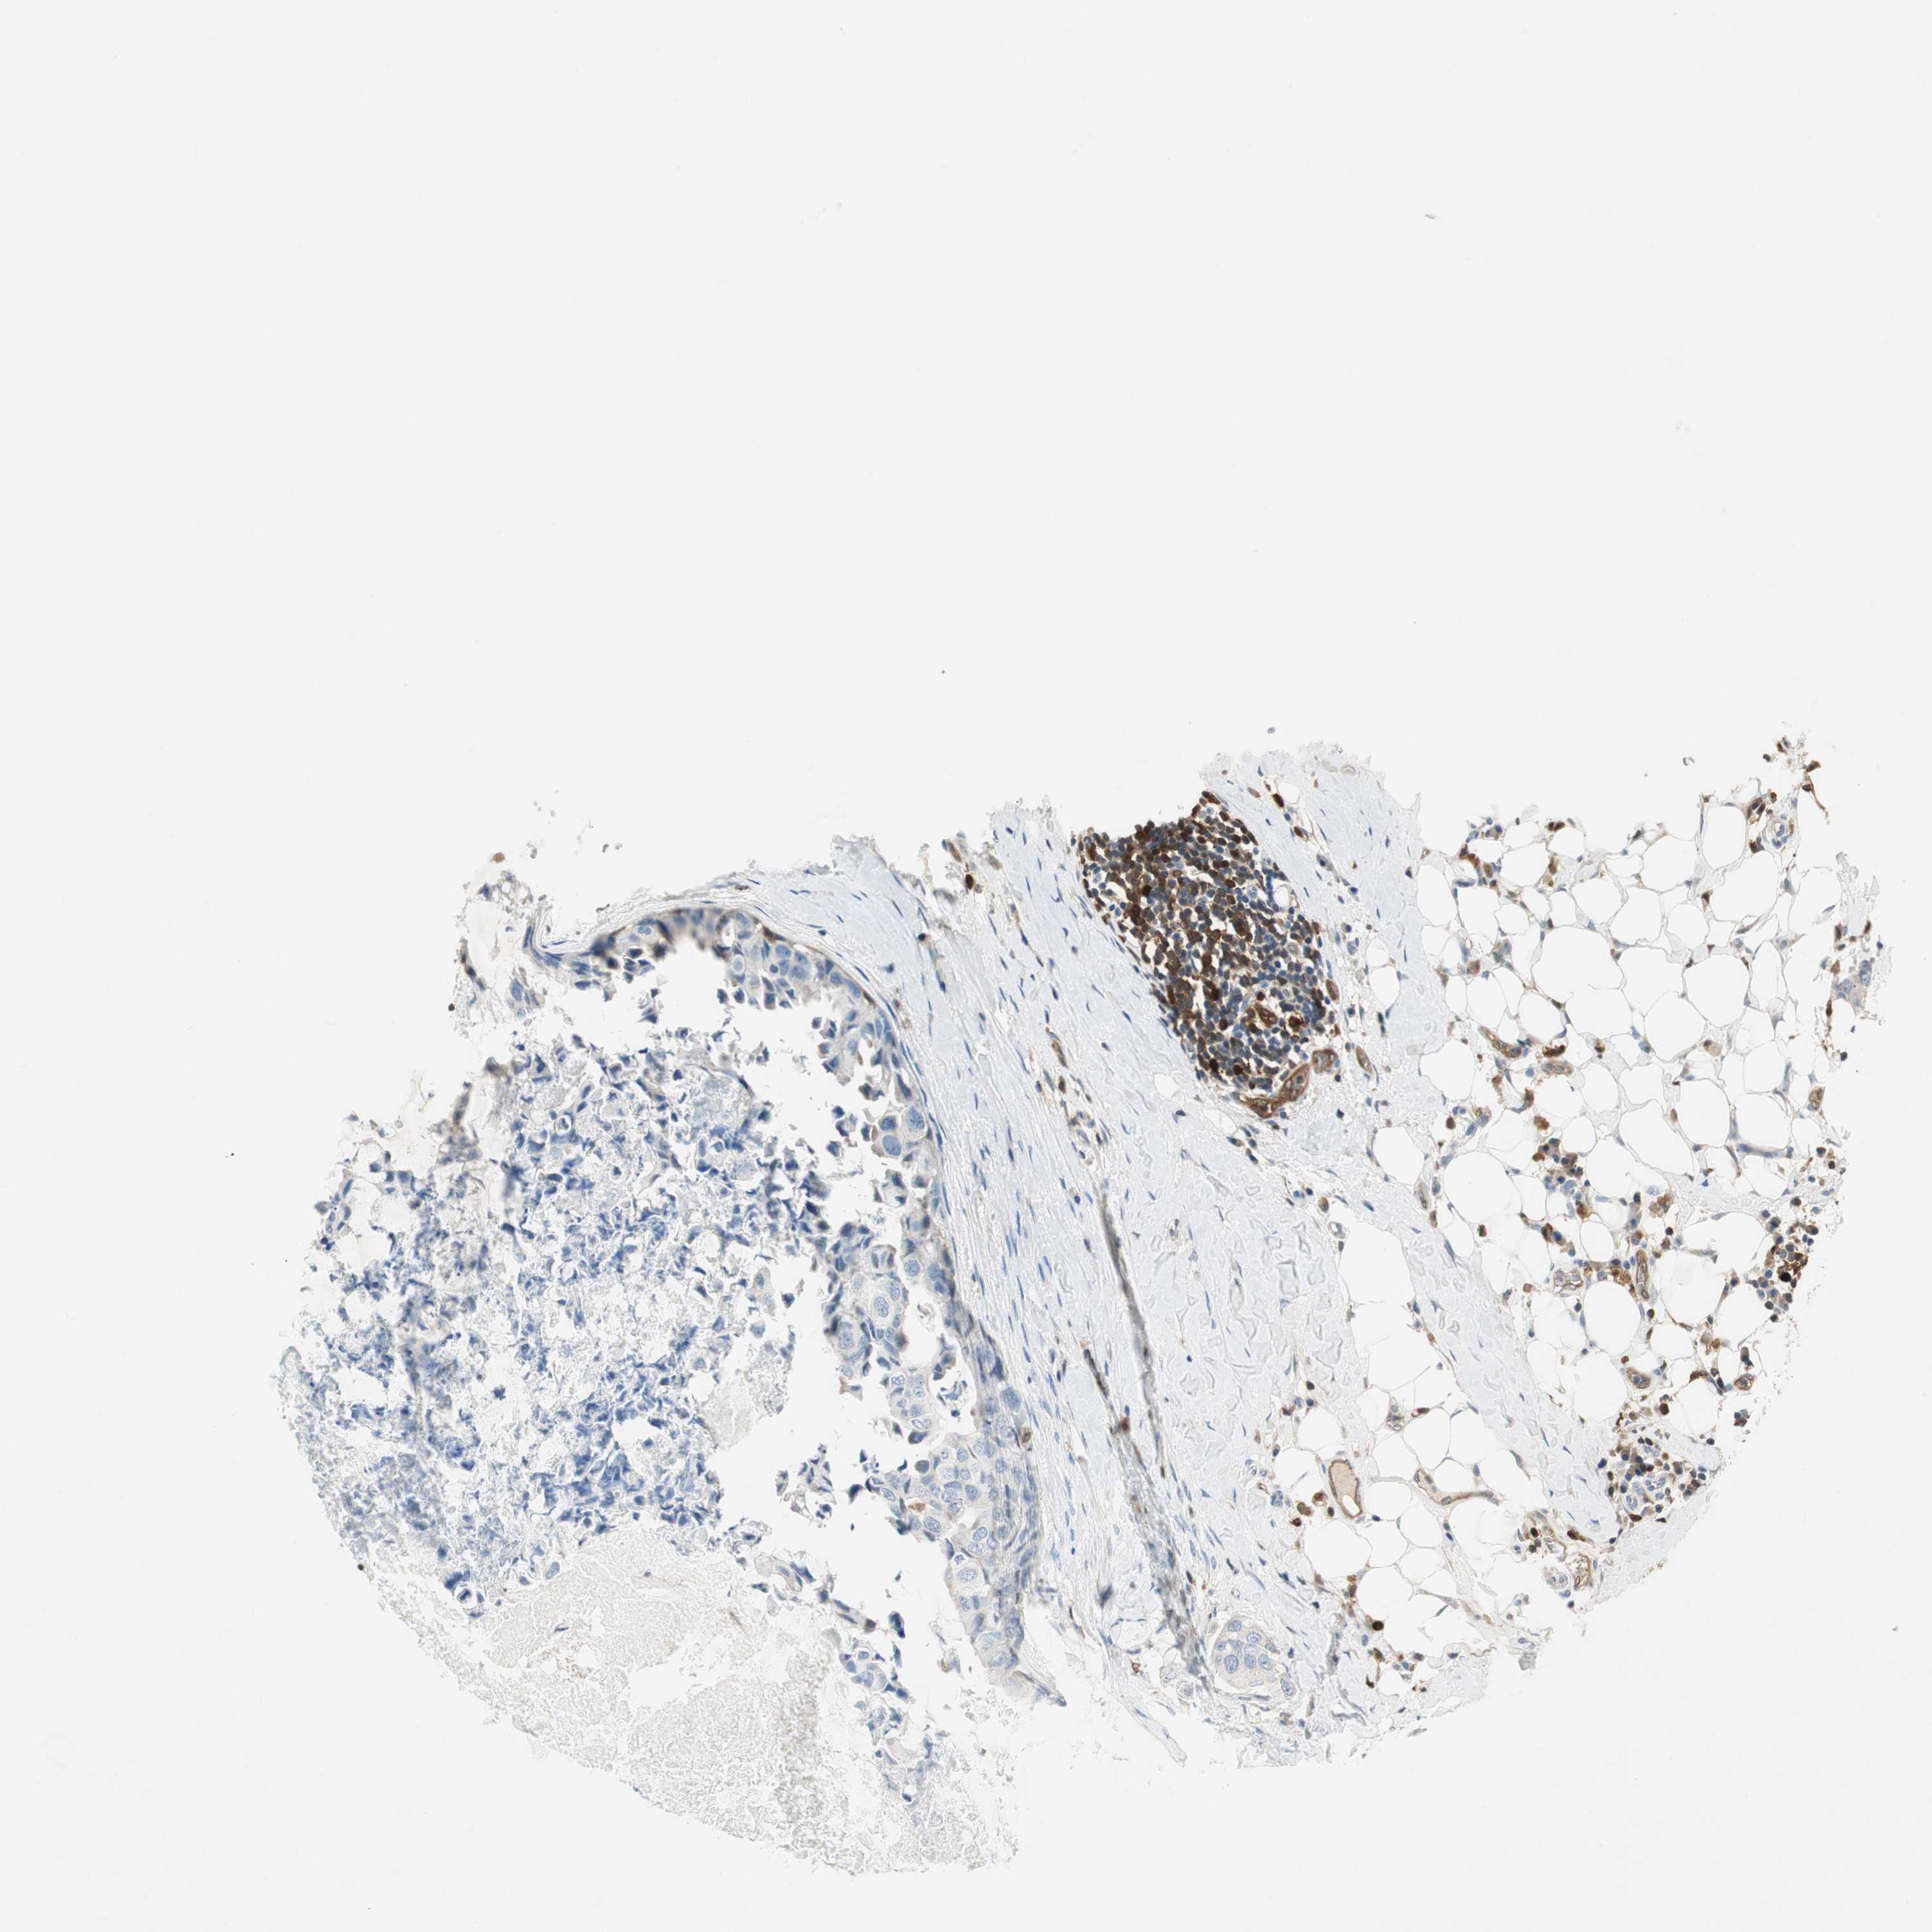

BRCA TCGA BRCA VALIDATION PROTEIN EXPRESSION